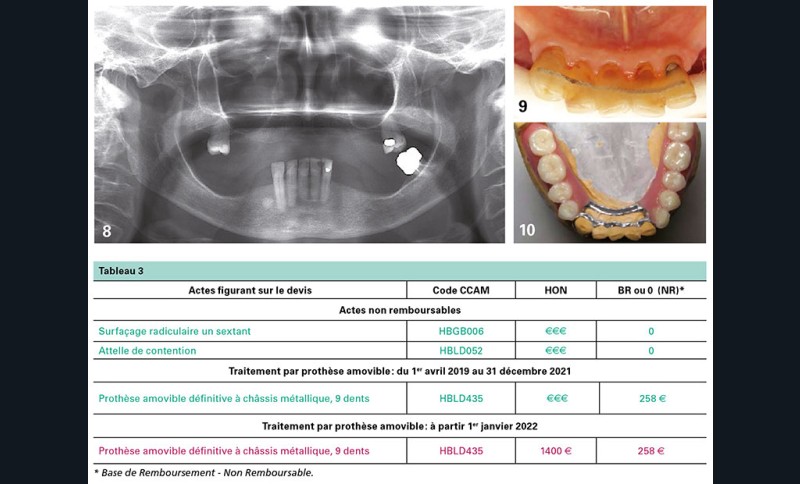

Une patiente, âgée de 76 ans, a une prothèse maxillaire squelettée de 12 dents, satisfaisante (fig. 8 à 10).

La prothèse mandibulaire est cassée. Le traitement prothétique à proposer ne peut ignorer l’état des dents résiduelles : 38 est à extraire et le bloc antérieur doit être assaini.

Sa consolidation et sa maintenance doivent être assurées pour optimiser une rétention non iatrogène de la prothèse amovible (tableau 3).